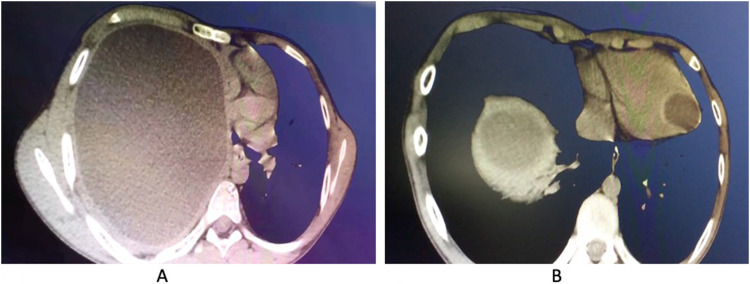

Hydatid cyst is a human parasitic disease caused by echinococcus granulosus that affects mainly the liver or the lungs but may be found in any organ, including the heart in up to 2% of the cases. Humans are infected as accidental hosts by contaminated vegetables or water and by contact with saliva from infected animals. Although cardiac echinococcosis can be fatal, it is rare and often asymptomatic in the early stage. We present the case of a young boy living on a farm who suffered from mild exertional dyspnea. He suffered from pulmonary and cardiac echinococcosis and was treated surgically through median sternotomy to prevent potential cystic rupture.